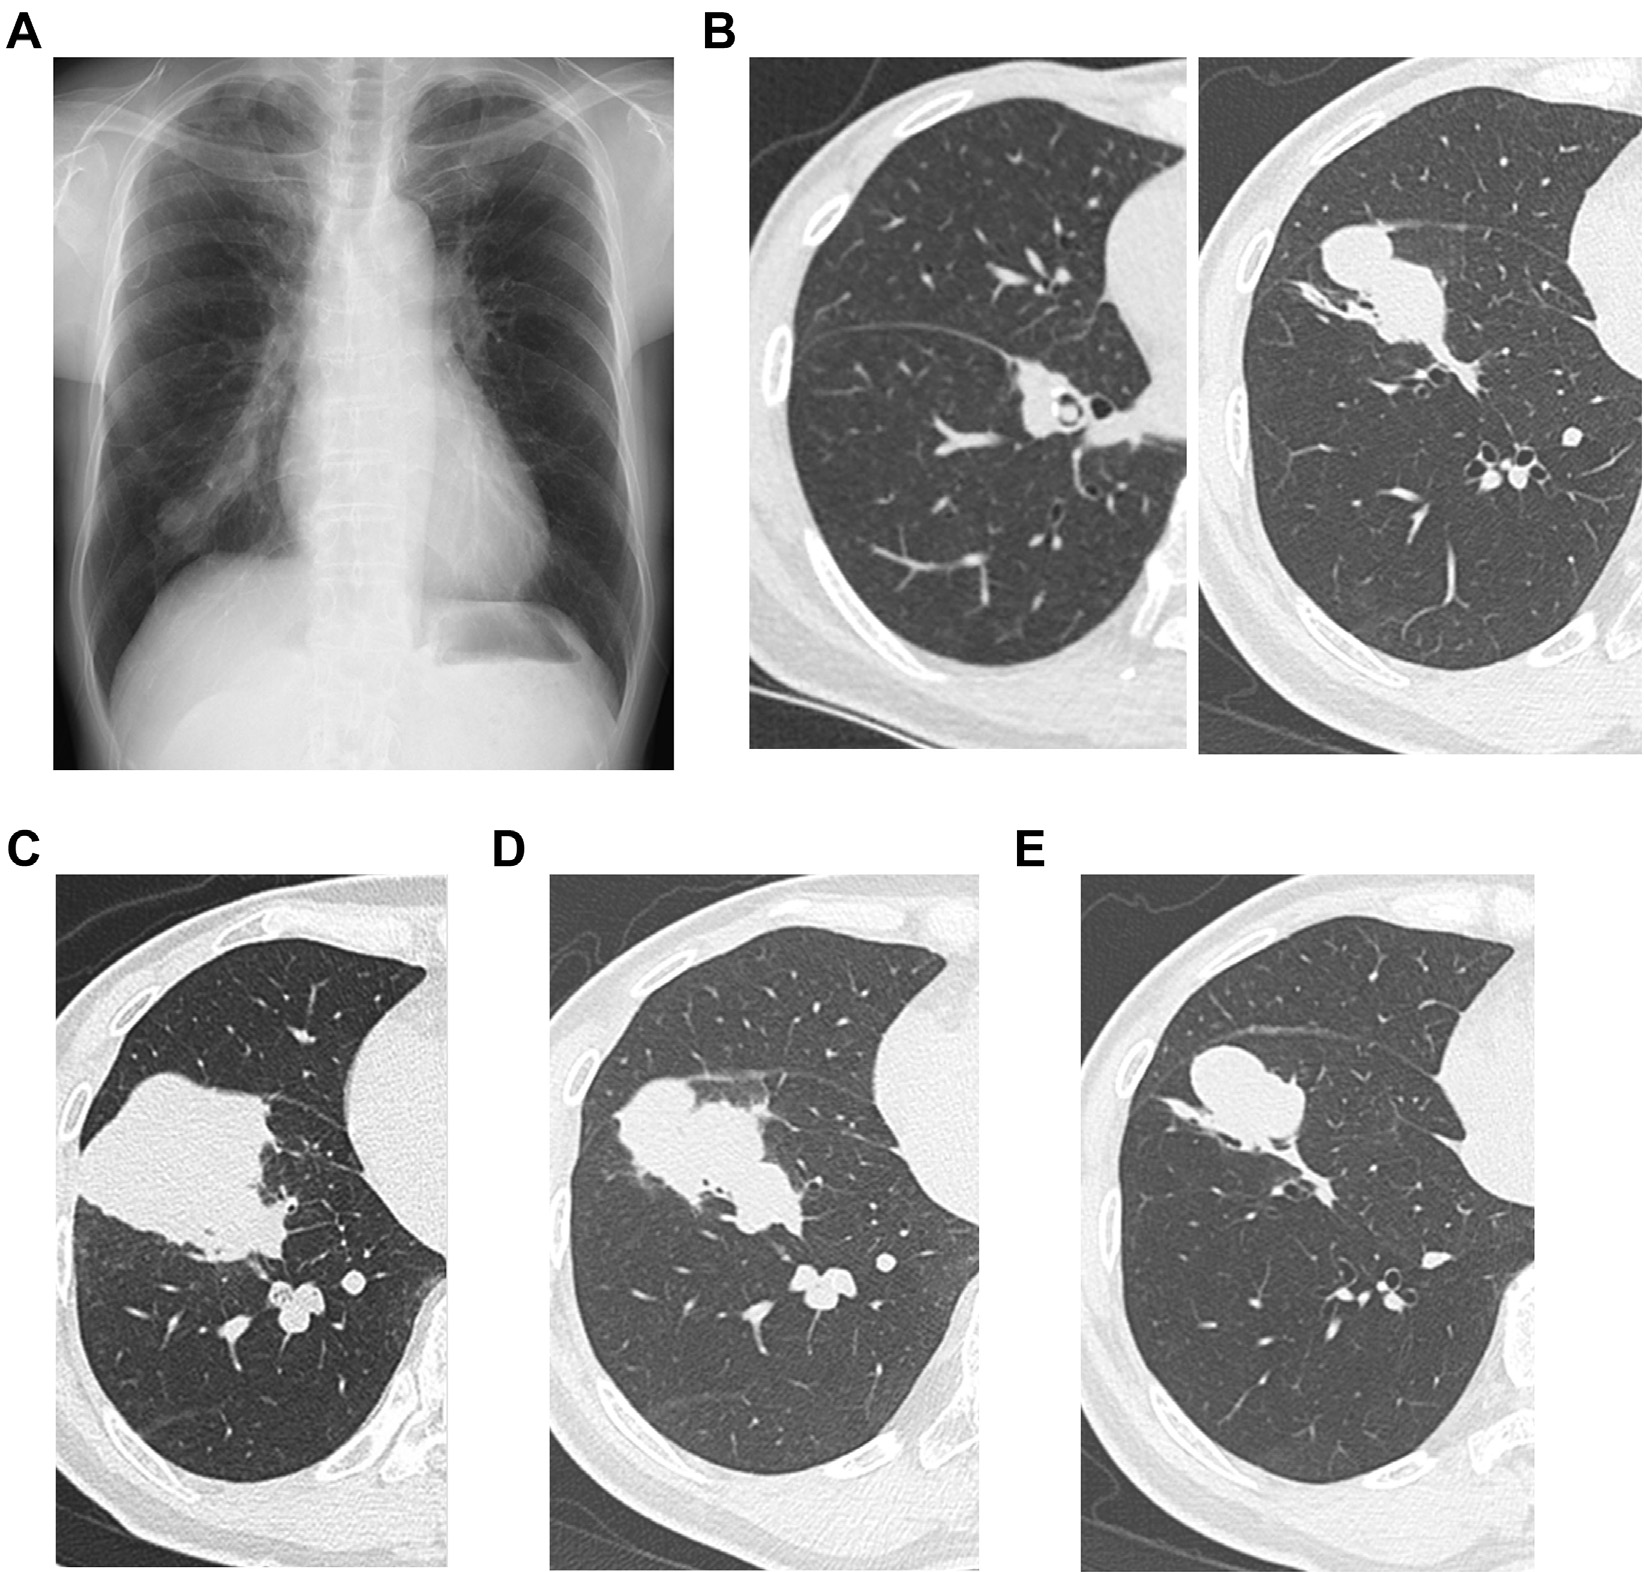

胸片和CT显示右肺下叶浸润影,与支气管血管束相连(图1A和B)。与9个月前的CT检查

结果相比(图1C),浸润性阴影的范围逐渐减小(图1D和E);但类似雪人状的阴影仍然存在(图1B)。此外,在右下叶基底段支气管内可见到黏液栓样结构,一直延伸至前基底段支气管(B8),提示肺炎后发生了黏液嵌塞(图1B)。

图1 A-E,胸部影像学结果。A,第一次来我院时的胸片显示右肺下叶实变;B-E,胸部CT显示右下叶实变(B,首次来我院就诊;C,首次就诊前9个月;d,首次就诊前6个月;e,首次就诊前3个月)。